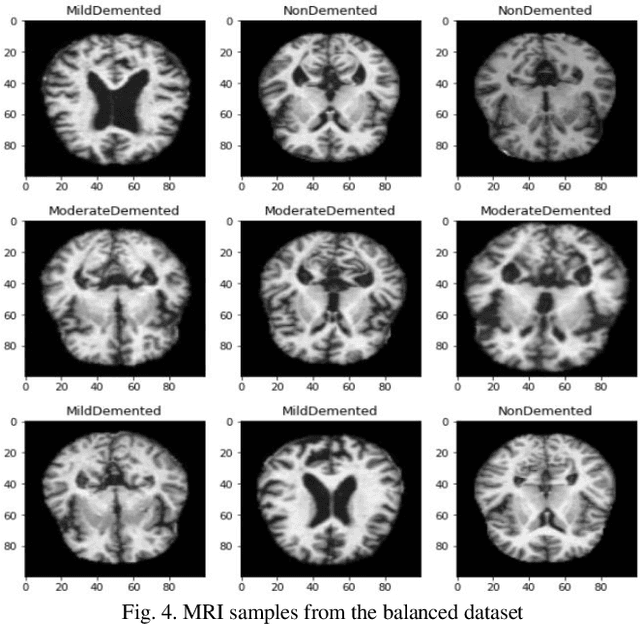

Abstract:Objective: This paper presents an Alzheimer's disease (AD) detection method based on learning structural similarity between Magnetic Resonance Images (MRIs) and representing this similarity as a graph. Methods: We construct the similarity graph using embedded features of the input image (i.e., Non-Demented (ND), Very Mild Demented (VMD), Mild Demented (MD), and Moderated Demented (MDTD)). We experiment and compare different dimension-reduction and clustering algorithms to construct the best similarity graph to capture the similarity between the same class images using the cosine distance as a similarity measure. We utilize the similarity graph to present (sample) the training data to a convolutional neural network (CNN). We use the similarity graph as a regularizer in the loss function of a CNN model to minimize the distance between the input images and their k-nearest neighbours in the similarity graph while minimizing the categorical cross-entropy loss between the training image predictions and the actual image class labels. Results: We conduct extensive experiments with several pre-trained CNN models and compare the results to other recent methods. Conclusion: Our method achieves superior performance on the testing dataset (accuracy = 0.986, area under receiver operating characteristics curve = 0.998, F1 measure = 0.987). Significance: The classification results show an improvement in the prediction accuracy compared to the other methods. We release all the code used in our experiments to encourage reproducible research in this area